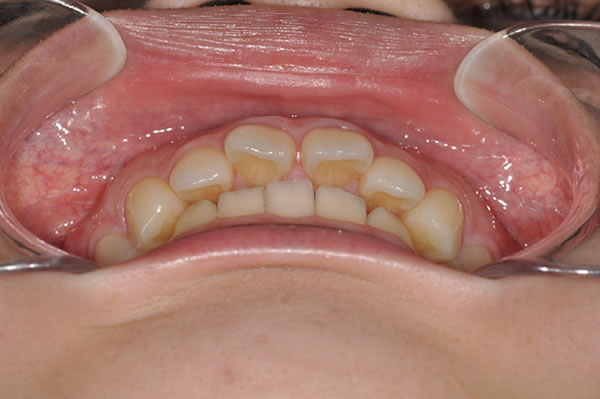

上顎前突症(出っ歯)の矯正症例 ケース01

| 治療前(初診) | 治療後 | |